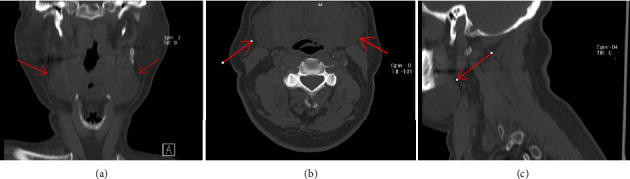

COVID-19 is associated with a hypercoagulable state, often managed with anticoagulation therapy to prevent thrombotic events. However, anticoagulation can lead to rare but serious bleeding complications. We present the case of a 62-year-old male with severe COVID-19 admitted to the intensive care unit (ICU) with shortness of breath, cough, and oxygen desaturation. Also, he had diabetes, undergoing treatment with Neutral Protamine Hagedorn (NPH) insulin, and ischemic heart disease. On the eighth day of his admission, he developed a spontaneous sublingual hematoma while on unfractionated heparin therapy. The patient was managed conservatively with blood pressure control, cold compresses, adjustment of anticoagulation and close monitoring with laboratory anticoagulation tests, and careful observation. Despite the hematoma's initial enlargement, he exhibited no respiratory distress, and the hematoma gradually resolved without surgical intervention. This case highlights the need for vigilant monitoring, careful management of anticoagulation, and a multidisciplinary approach in balancing the benefits and risks of anticoagulation in COVID-19 patients.

Abstract Image